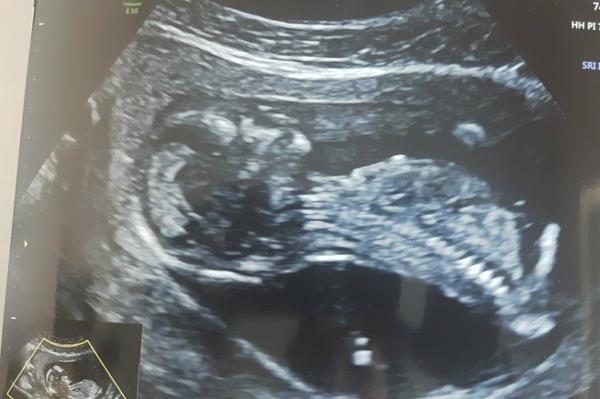

jsem na webu poprvé a hned mám otázku. Poznáte z ultrazvuku jaká budeme mít pohlaví? Jsem v 13tt a čekáme dvojvaječná dvojčátka- takže kombina jakákoliv 😀. Dneska mi paní doktorka sdělila co vidí, ale nebyla si úplně jistá 😀 proto bych chtěla znát vás názor co si myslíte vy.

Ahoj, tipuji horni kluk a druhe holcicka? 😀

Ahoj , tipuju to same, horni je kluk, druhy obrazek holka??

tipuju dva chlapáky

Myslím, že dole je holčička, ale první netuším.

Holčička a kluk?